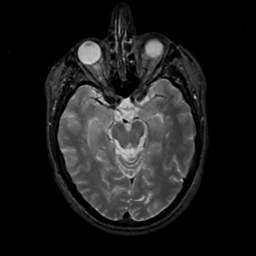

MR Study #3, February 24, 1991 -- Slice #19

[Home][Help][Clinical][Tour 1][Tour 2] Slice 19